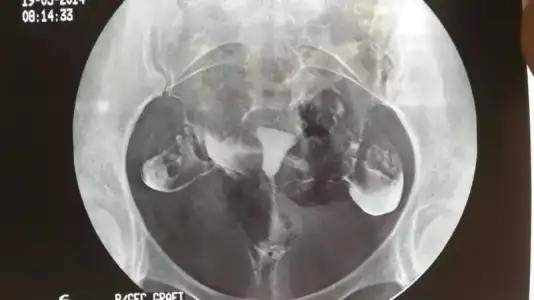

Benimki de bu sekilde raporda rahimin normal form ve hacimde oldugu verilen maddenin tuplerden serbest olarak dagildigi tuplerin normal capta oldugu herhangi bir patolojik bulgu saptanmadgi yaziyr

Senin film çok kaliteli yalnız.. Bende de su yazıyor madde sol tubadan geçip peritonaya ulaştı sağda madde geçişi azaldı..